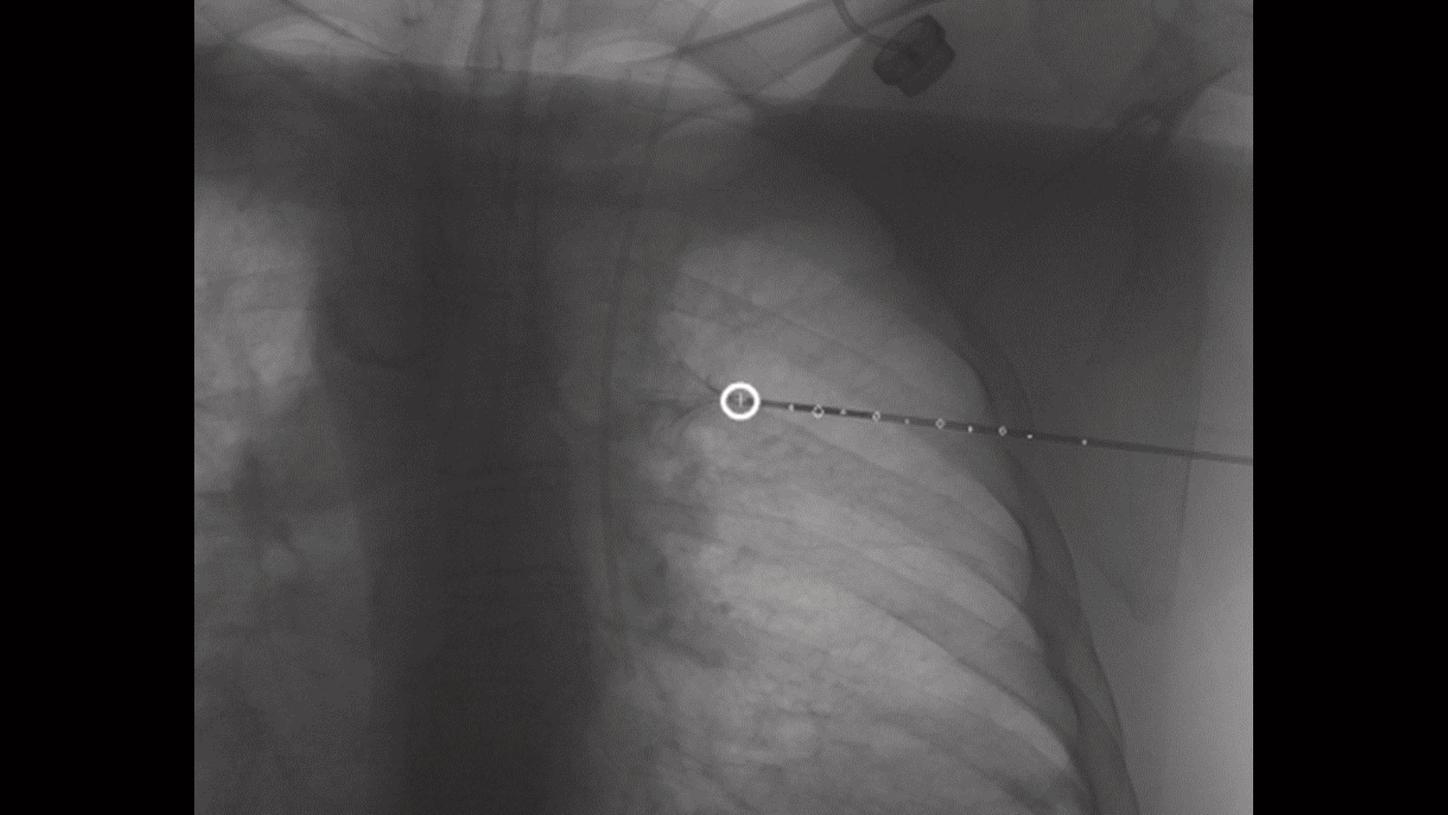

Visualisation claire lors des interventions hyper-sélectives

Notre technologie OPTIQ, système de régulation qui se base sur la qualité image choisie, permet d’obtenir un contraste optimal avec la dose la plus faible possible*, pour une bonne visibilité des petits vaisseaux et des dispositifs en imagerie 2D. OPTIQ inclut Structure Scout, qui adapte le spectre des rayons X aux caractéristiques d’absorption du matériau utilisé.

OPTIQ DSA a été développé de manière à améliorer la visibilité en imagerie soustraite, en renforçant la netteté et le contraste sans accroître le bruit.